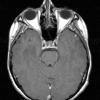

NEOPLASMS (GLIAL)

Astrocytoma, IDH-mutant, WHO Grade 2 (12)